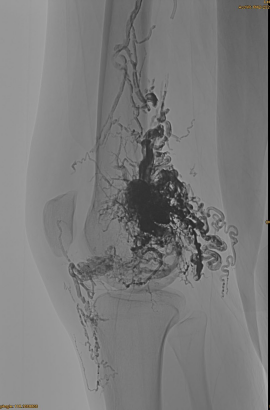

Αρχικό DSA:

Τελικό αποτέλεσμα:

Σχεδόν καθόλου φλεβική εκροή:

Καθυστερημένη φάση, ένα άλλο Embo είναι απαραίτητο, αλλά πολύ καλύτερα: